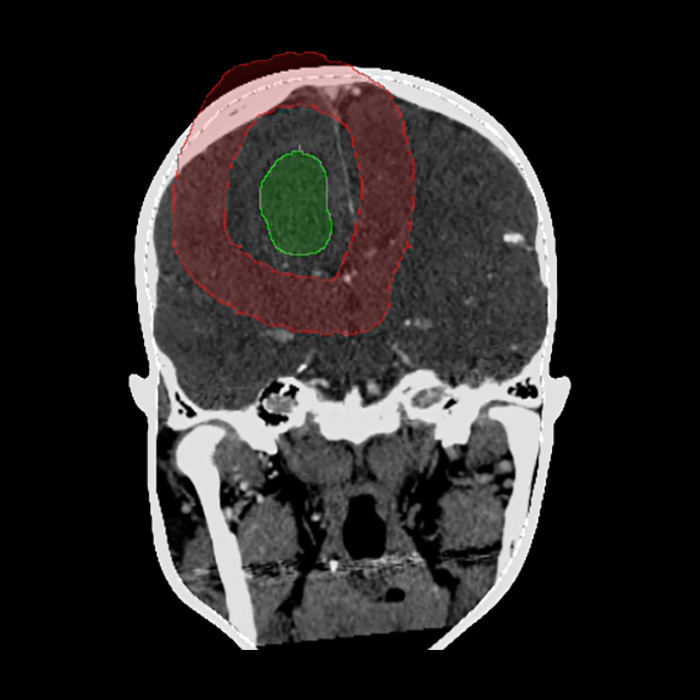

The user interface was custom designed to leverage the power of the software tools in a form which is intuitive and user friendly and provides the key clinical functionality. During the planning stage, for example, the user is walked through tasks such as skin segmentation, lesion and trajectory delineation, and landmark selection to be used for registration.

Pre-op Planning

Skin Segmentation

Target Segmentation

Trajectory Planning